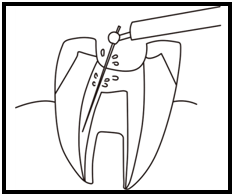

Q1.痛みはありますか? ② 次に、「根管長測定器」という機械を使い、根っこの長さを正確に測ります。

② 次に、「根管長測定器」という機械を使い、根っこの長さを正確に測ります。